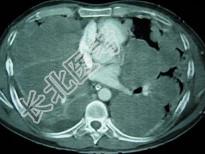

- 单项选择题33岁,男, 咳嗽1周,有骨肉瘤病史, 请结合胸片和CT图,选出最可能的诊断 ( )

C、骨肉瘤转移